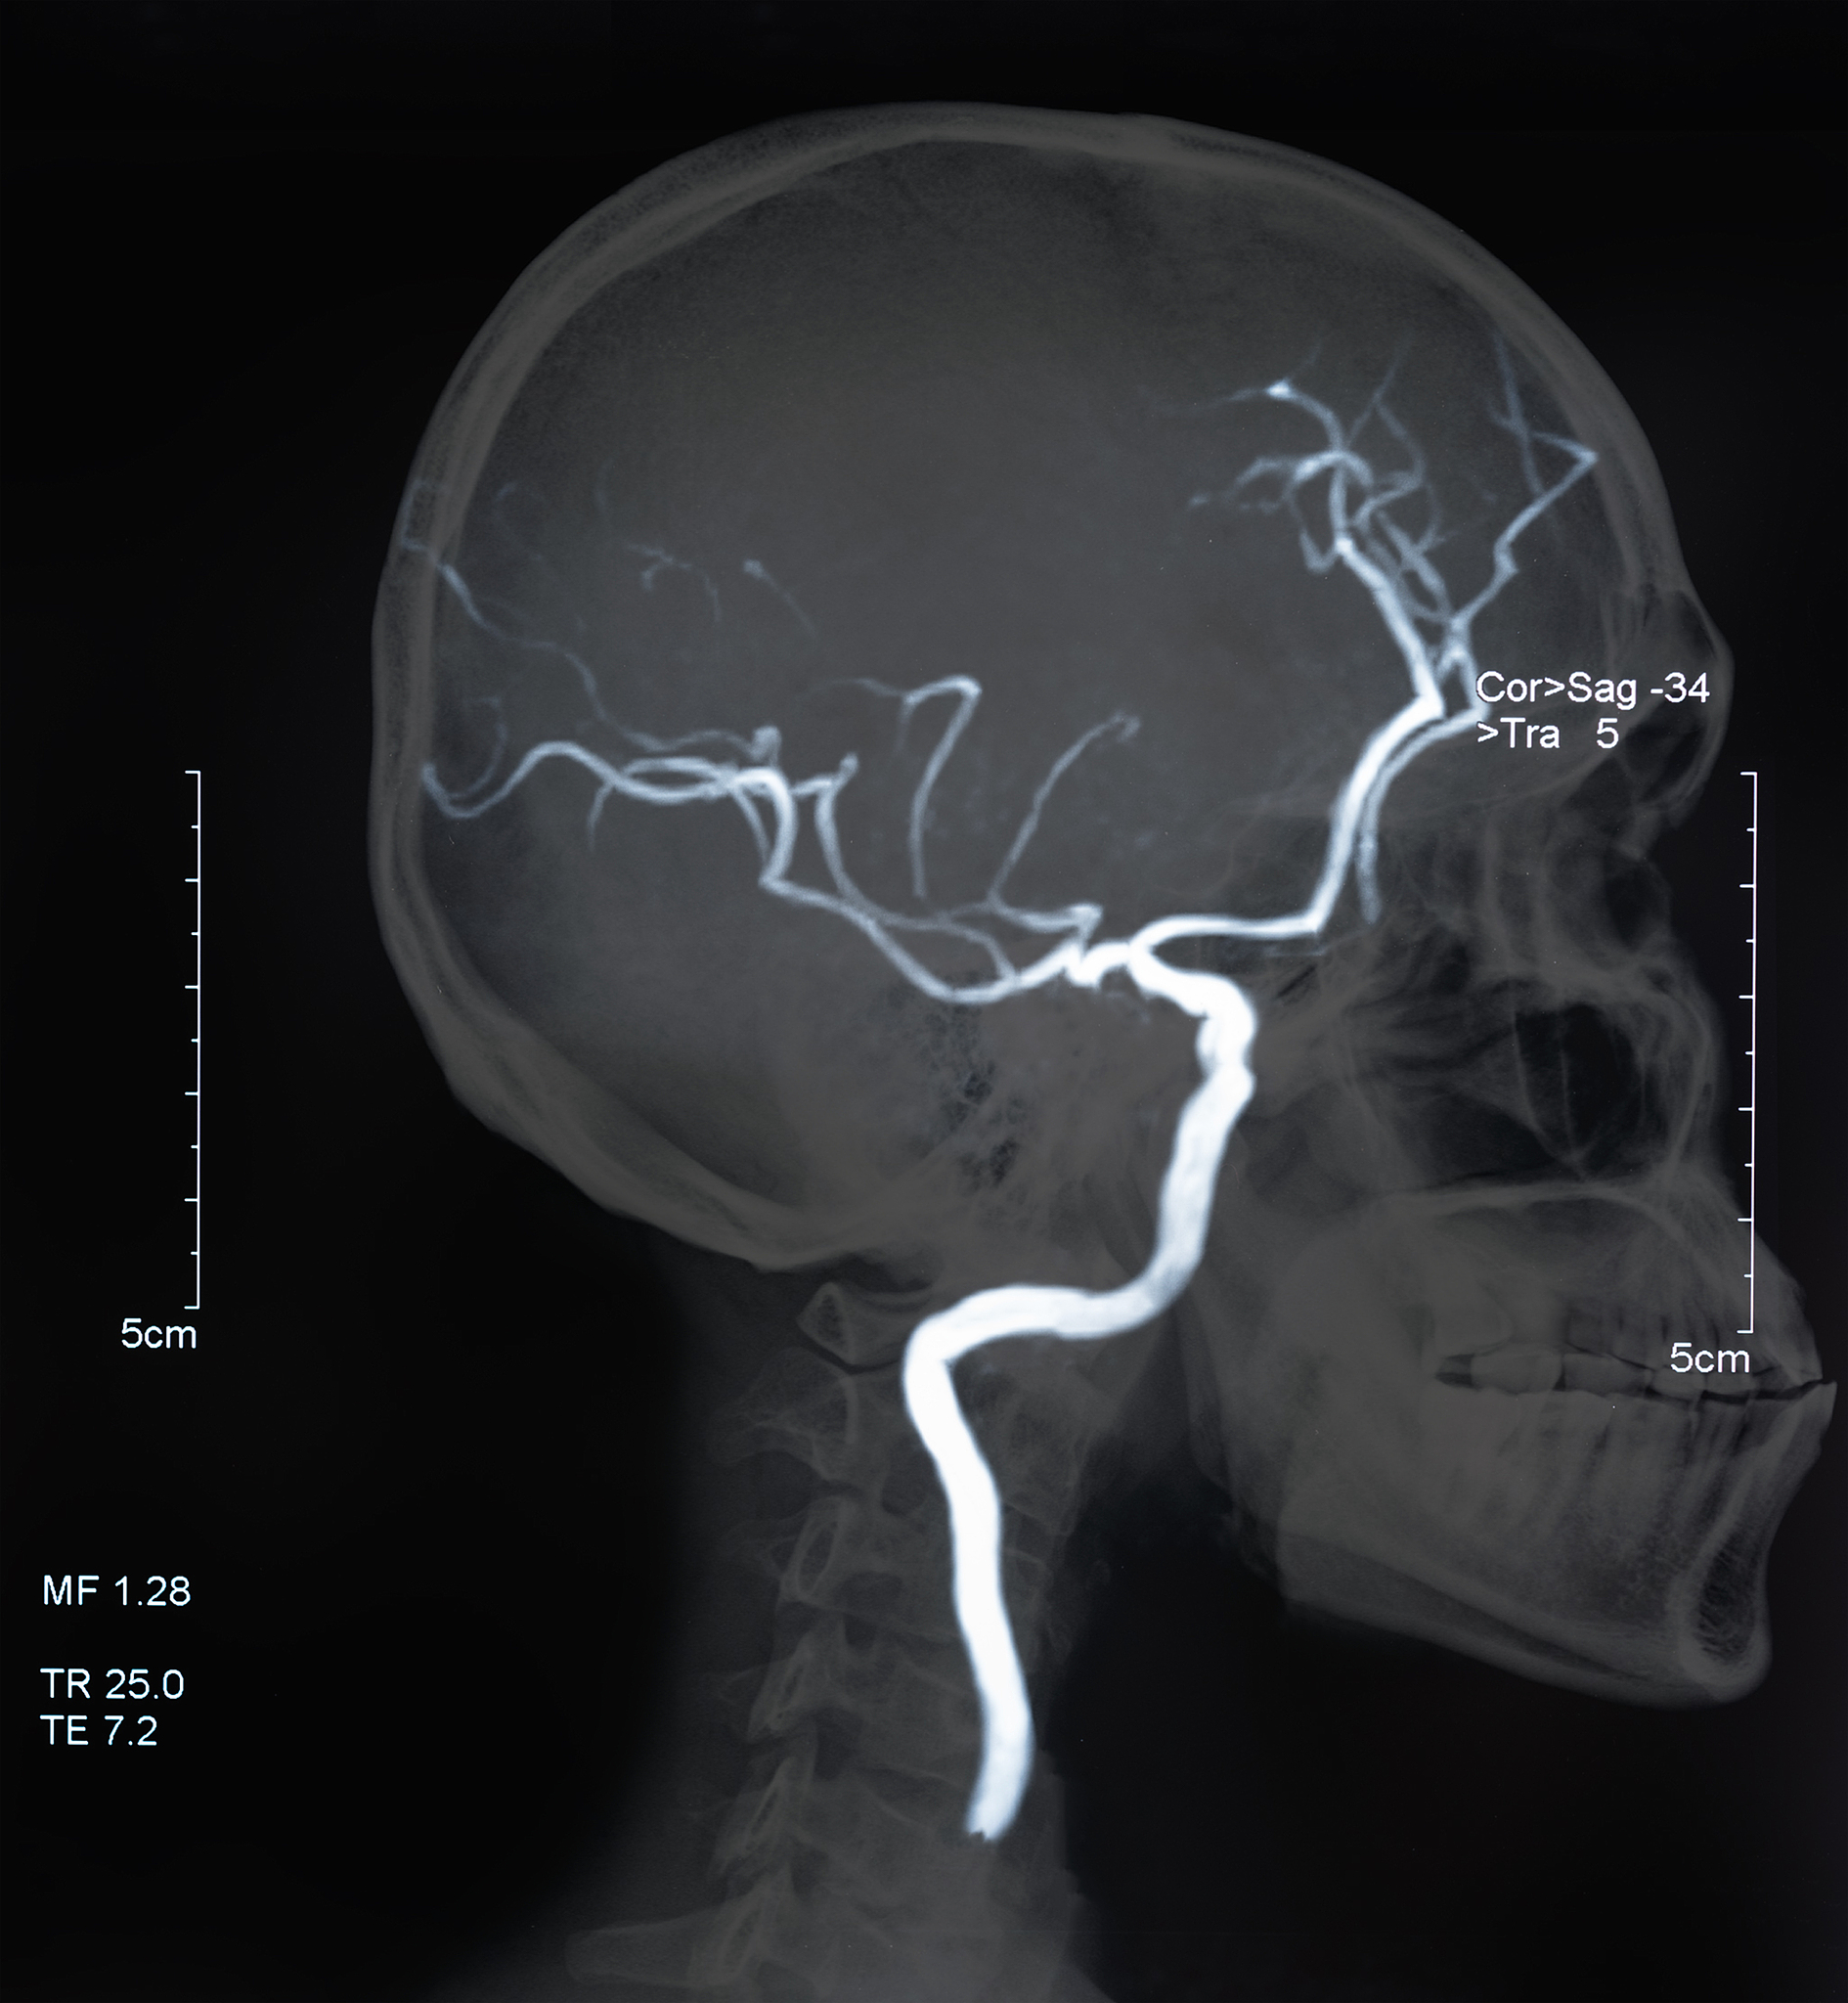

颈动脉甜甜圈征:CTA图像上的填充缺损

在CTA的至少两个轴向源图像中,颈动脉内的FFT出现,其中颈动脉管腔内的充盈缺损完全被造影剂包围,被描述为'甜甜圈征'。